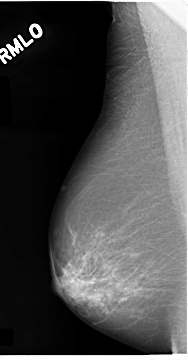

C_0074_1.RIGHT_MLO

RIGHT_CC LINES 4648 PIXELS_PER_LINE 2520 BITS_PER_PIXEL 12 RESOLUTION 50 NON_OVERLAY

RIGHT_MLO LINES 4672 PIXELS_PER_LINE 2432 BITS_PER_PIXEL 12 RESOLUTION 50 NON_OVERLAY